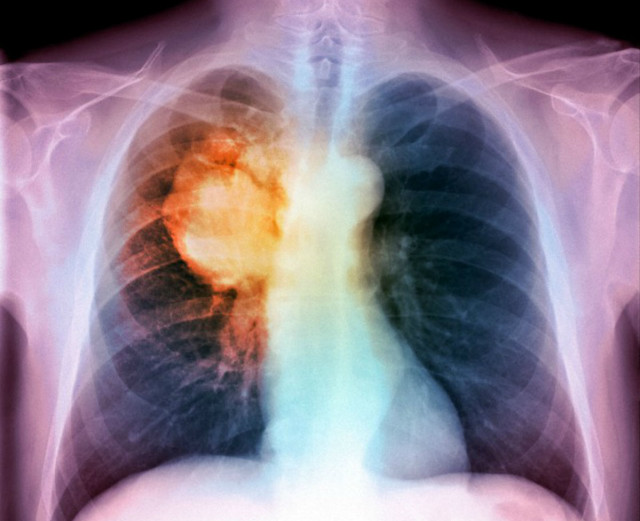

Nuovo approccio per il trattamento del carcinoma polmonare a piccole cellule

I ricercatori dell’ Anderson Cancer Center dell’Università del Texas hanno scoperto che una combinazione del blocco del checkpoint immunitario e terapie mirate che bloccano la normale riparazione del danno del DNA (DDR) hanno ottenuto una significativa regressione del carcinoma polmonare a piccole cellule nei modelli murini (SCLC), suggerendo un promettente nuovo approccio per il trattamento di pazienti con questo tumore aggressivo.